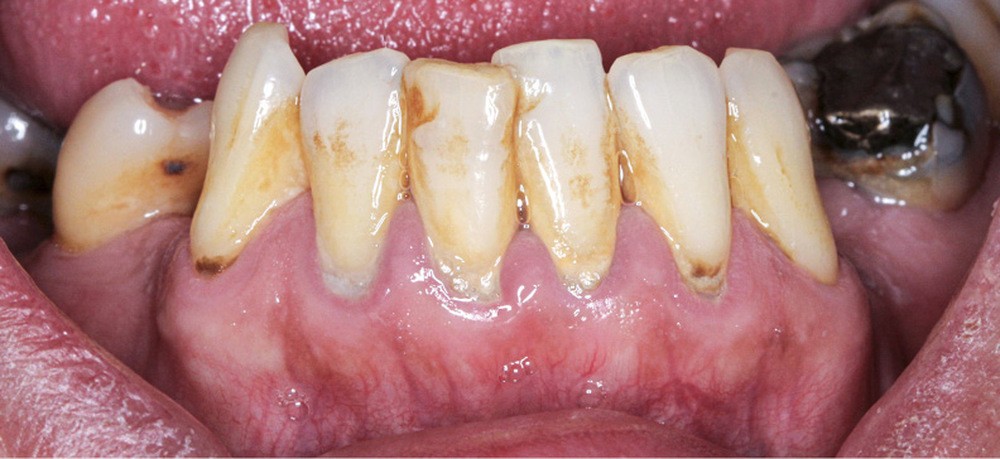

L’obésité, définie par un indice de masse corporelle (IMC) ≥ 30 kg/m2, est une maladie inflammatoire chronique complexe et multifactorielle caractérisée par un dépôt excessif de graisse dans le tissu adipeux. Selon l’OMS, depuis 1975, le nombre de cas d’obésité a presque triplé à l’échelle planétaire [1]. En 2020, près d’un Français sur deux était en surpoids, tandis que 17 % étaient obèses [2]. Or l’obésité est responsable d’une haute mortalité à l’échelle mondiale et est un facteur de risque majeur pour de nombreuses maladies, dont les maladies cardiovasculaires, le diabète de type 2 et certains cancers [1]. Son impact sur la santé des populations et son coût économique et social sont donc considérables. Ces deux dernières décennies, de nombreuses études ont montré que l’obésité pouvait aussi être incriminée dans la détérioration de la santé bucco-dentaire [3] (fig. 1 à 7).